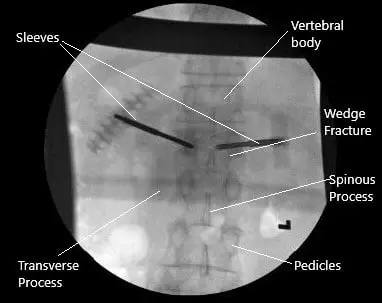

Intraoperative X-ray of the kyphoplasty.

C-arm was brought in and the L1 vertebra was localized in the AP and lateral view. The pedicles of the L1 vertebra were localized on both sides. A spinal needle was used to make an entry through the facet joint into the pedicle. Bilateral entries were made to the lateral pedicles.

Once the Jamshidi needles were on the medial pedicle, the lateral view was checked and they were found to be in a satisfactory position. The Jamshidi needles were advanced further. A bone biopsy was taken from the medial vertebrae and sent for histopathology.

Once we found the Jamshidi needles in appropriate position, the Jamshidi needles were removed. The sleeves were withdrawn by about a centimeter and balloons were inserted on both sides. The balloons were inflated. We felt that there was a breach on the inferior endplate on the right side, so the inflation was stopped at that time.